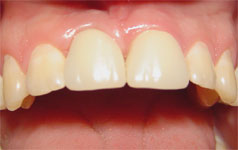

El primer paso consiste en colocar pilares protésicos y comprobar radiográficamente su correcto asentamiento (generalmente UCLA metálicos o bien existen sistemas que presentan cilindros plásticos para la confección de provisionales). Se confecciona acrílico autopolimerizable y al llegar a su estado plástico se realiza un dado que es adaptado sobre el pilar protésico. En boca y ayudado por una espátula se va dando forma. Al polimerizar se retira el provisional de la boca y con puntas montadas se eliminan los excesos de acrílico. Es importante que la remoción del acrílico sea relizada con puntas de corte fino que dejan una superficie más lisa favoreciendo una textura final más uniforme. Si se necesita hacer retoques se realizan por la técnica del pincel. Los ajustes oclusales son realizados con papel de articular y fresas esféricas. El 1/3 cervical debe tener un acabado con puntas de granos extras finos y gomas. Una vez terminado el acabado el provisional debe ser pulido con piedra pómez y agua con cepillos y ruedas de fieltro, hasta lograr una superficie de textura brillante.    Figuras 1, 2 y 3

EPÍGRAFES Figuras 1, 2 y 3: Método directo "a mano alzada" para confeccionar un contorno gingival correcto. Figuras 4, 5, 6 y 7: Método directo utilizando diente stock para permitir la remodelación ósea en implante "corto". Figuras 8, 9 y 10: Método directo empleando dientes de la prótesis removible del paciente. Figuras 11 y 12: Método directo empleando dientes de la prótesis removible del paciente utilizando cilindros plásticos. Figuras 13, 14 y 15: Método hibrido. Figuras 16, 17, 18, 19, 20: Método híbrido con el objeto de parcializar el tratamiento. Figuras 21, 22,23 y 24: Método indirecto con el propósito de brindar una solución económica y estética.